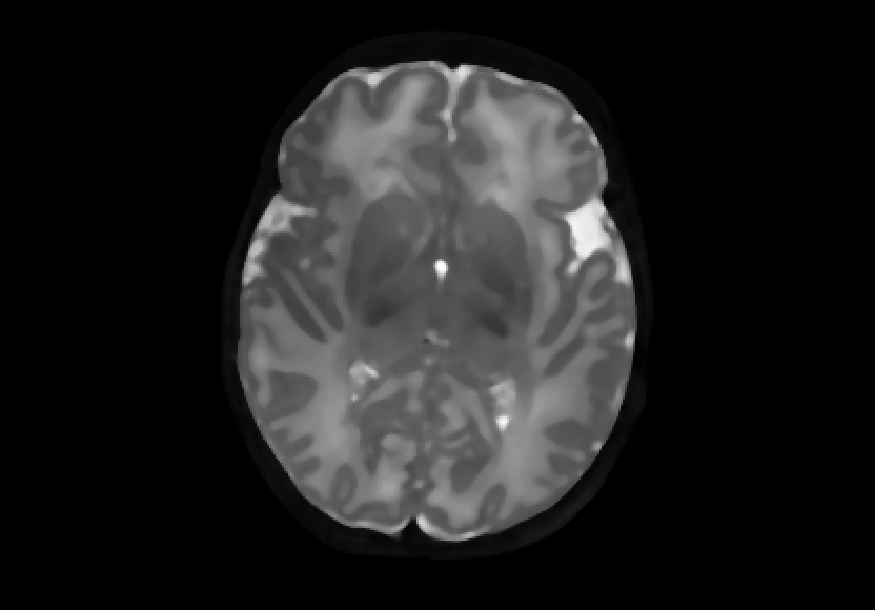

Second, we simulated further blur manifestations using median filters, which replace the pixel value with the median of the neighbouring pixels. We utilised filters from scipy [9], each with a parameter size that specifies the neighbourhood distance used to compute the median where higher values of size result in smoother filter output. Three different degrees of median filtered images with size= {2, 5, 8} were generated. Figure 3 shows examples of median-filtered images generated in this study.